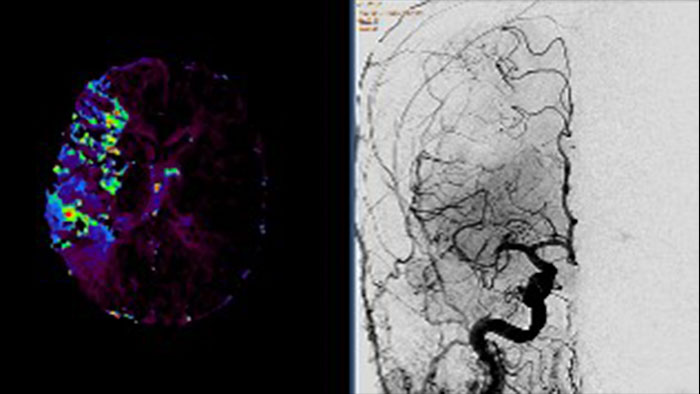

Tumor Tracking qEASL

Multi Modality Tumor Tracking qEASL (MMTT qEASL)

Semi-automatic tumor quantification

This semi-automated 3D (Volumetric) tumor response assessment tool, based on EASL (European Association for the Study of the Liver) criteria incorporates functional information from contrast-enhanced scans.

• Multi Modality Tumor Tracking supports the creation of Quantitative EASL (qEASL) maps used to measure segmented volumes of interest (VOI) in heterogeneous lesions.

• Data are presented as color map overlaid on the scans to show regional tumor enhancement heterogeneity. The color regions of the segmented lesions are where there is more enhancement than the pre-defined reference region.